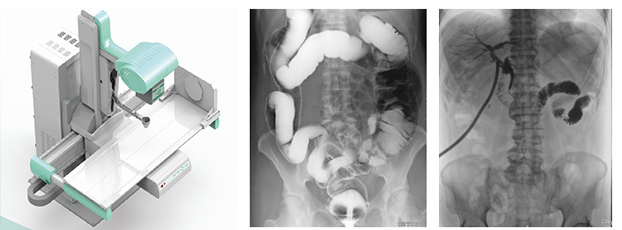

一、新一代動態(tài)平板探測器,一機多用實現(xiàn)動靜態(tài)采集

只需一塊動態(tài)平板探測器,即可高效輕松實現(xiàn)攝影、透視和造影功能,幾乎可以滿足醫(yī)院全科室的臨床檢查需求。

大尺寸動態(tài)平板技術,覆蓋檢查面積范圍廣,輕松實現(xiàn)胃十二指腸等大面積造影,無需移動即可觀看整個動態(tài)過程,避免噪點對圖像的影響。

3)高幀速

最高幀速可達30幀/秒,獲得與靜態(tài)采集相媲美的高清流暢影像;

采用先進的脈沖透視技術,呈現(xiàn)更優(yōu)圖像空間分辨率、低對比度分辨率、灰階范圍,為精準診斷提供可靠依據(jù)。

4)透視+高清點片

在可視過程或回放過程中,如發(fā)現(xiàn)疑似病灶,可進行毫秒級高清點片,隨時抓取單幀圖像,精準捕抓病灶,便于醫(yī)生進一步診斷分析,減少誤診,并有助于快速編制報告。